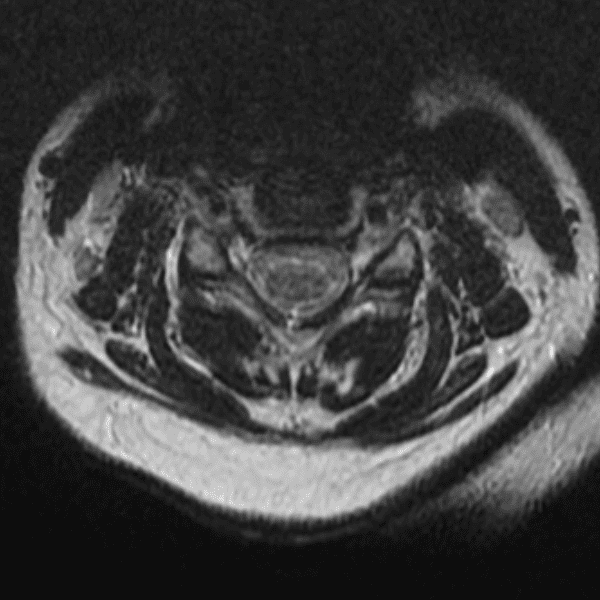

Simulates call by including subtle or difficult cases and some normals.

35 cases